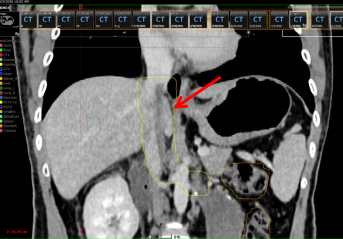

患者术后恢复良好,术后一周开始行一程碳离子治疗,剂量36Gy(RBE)/4Gy(RBE)/9Fx,一程碳离子放疗结束复查CT提示:癌栓明显缩退,上界已离开右心房,缩小到肝静脉汇集平面。目前已开始二程俯卧位碳离子放疗,碳离子治疗期间患者没有出现消化道放疗反应,一程+二程碳离子放疗总量达到72Gy(RBE),完成肾癌切除术后残留腔静脉癌栓碳离子根治性放疗。此次碳离子治疗前的隔离胶植入,充分体现了我院碳离子治疗的严谨性和精准性,始终将患者的获益放在第一位。

图7 一程治疗后癌栓缩退(图中红色箭头所指黄色框内区域)